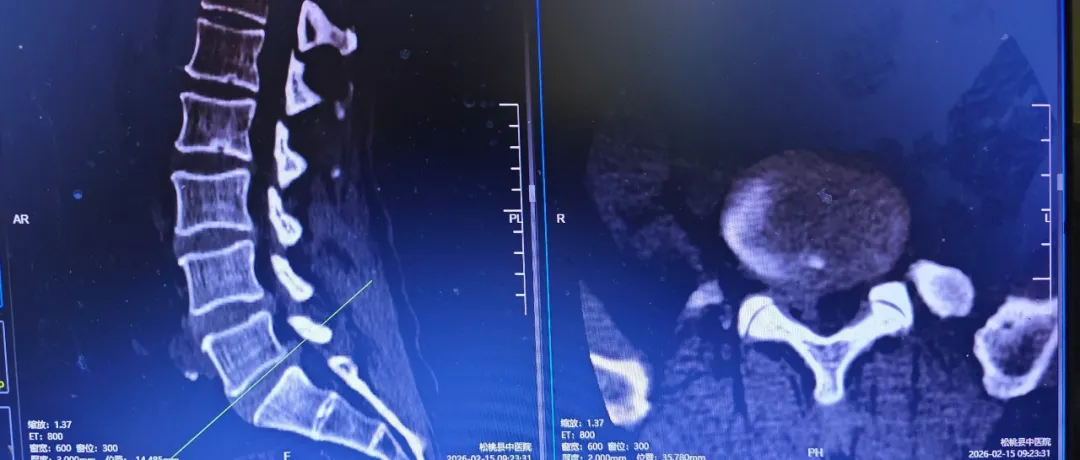

近日,62岁的王某因椎间盘突出症,经朋友介绍来到松桃苗族自治县民族中医院骨二科后,经科室团队为他行椎间孔镜微创手术,第二天能佩戴腰围下床走路,配合中(苗)医药治疗和口服助力康复,目前恢复良好,即将出院...